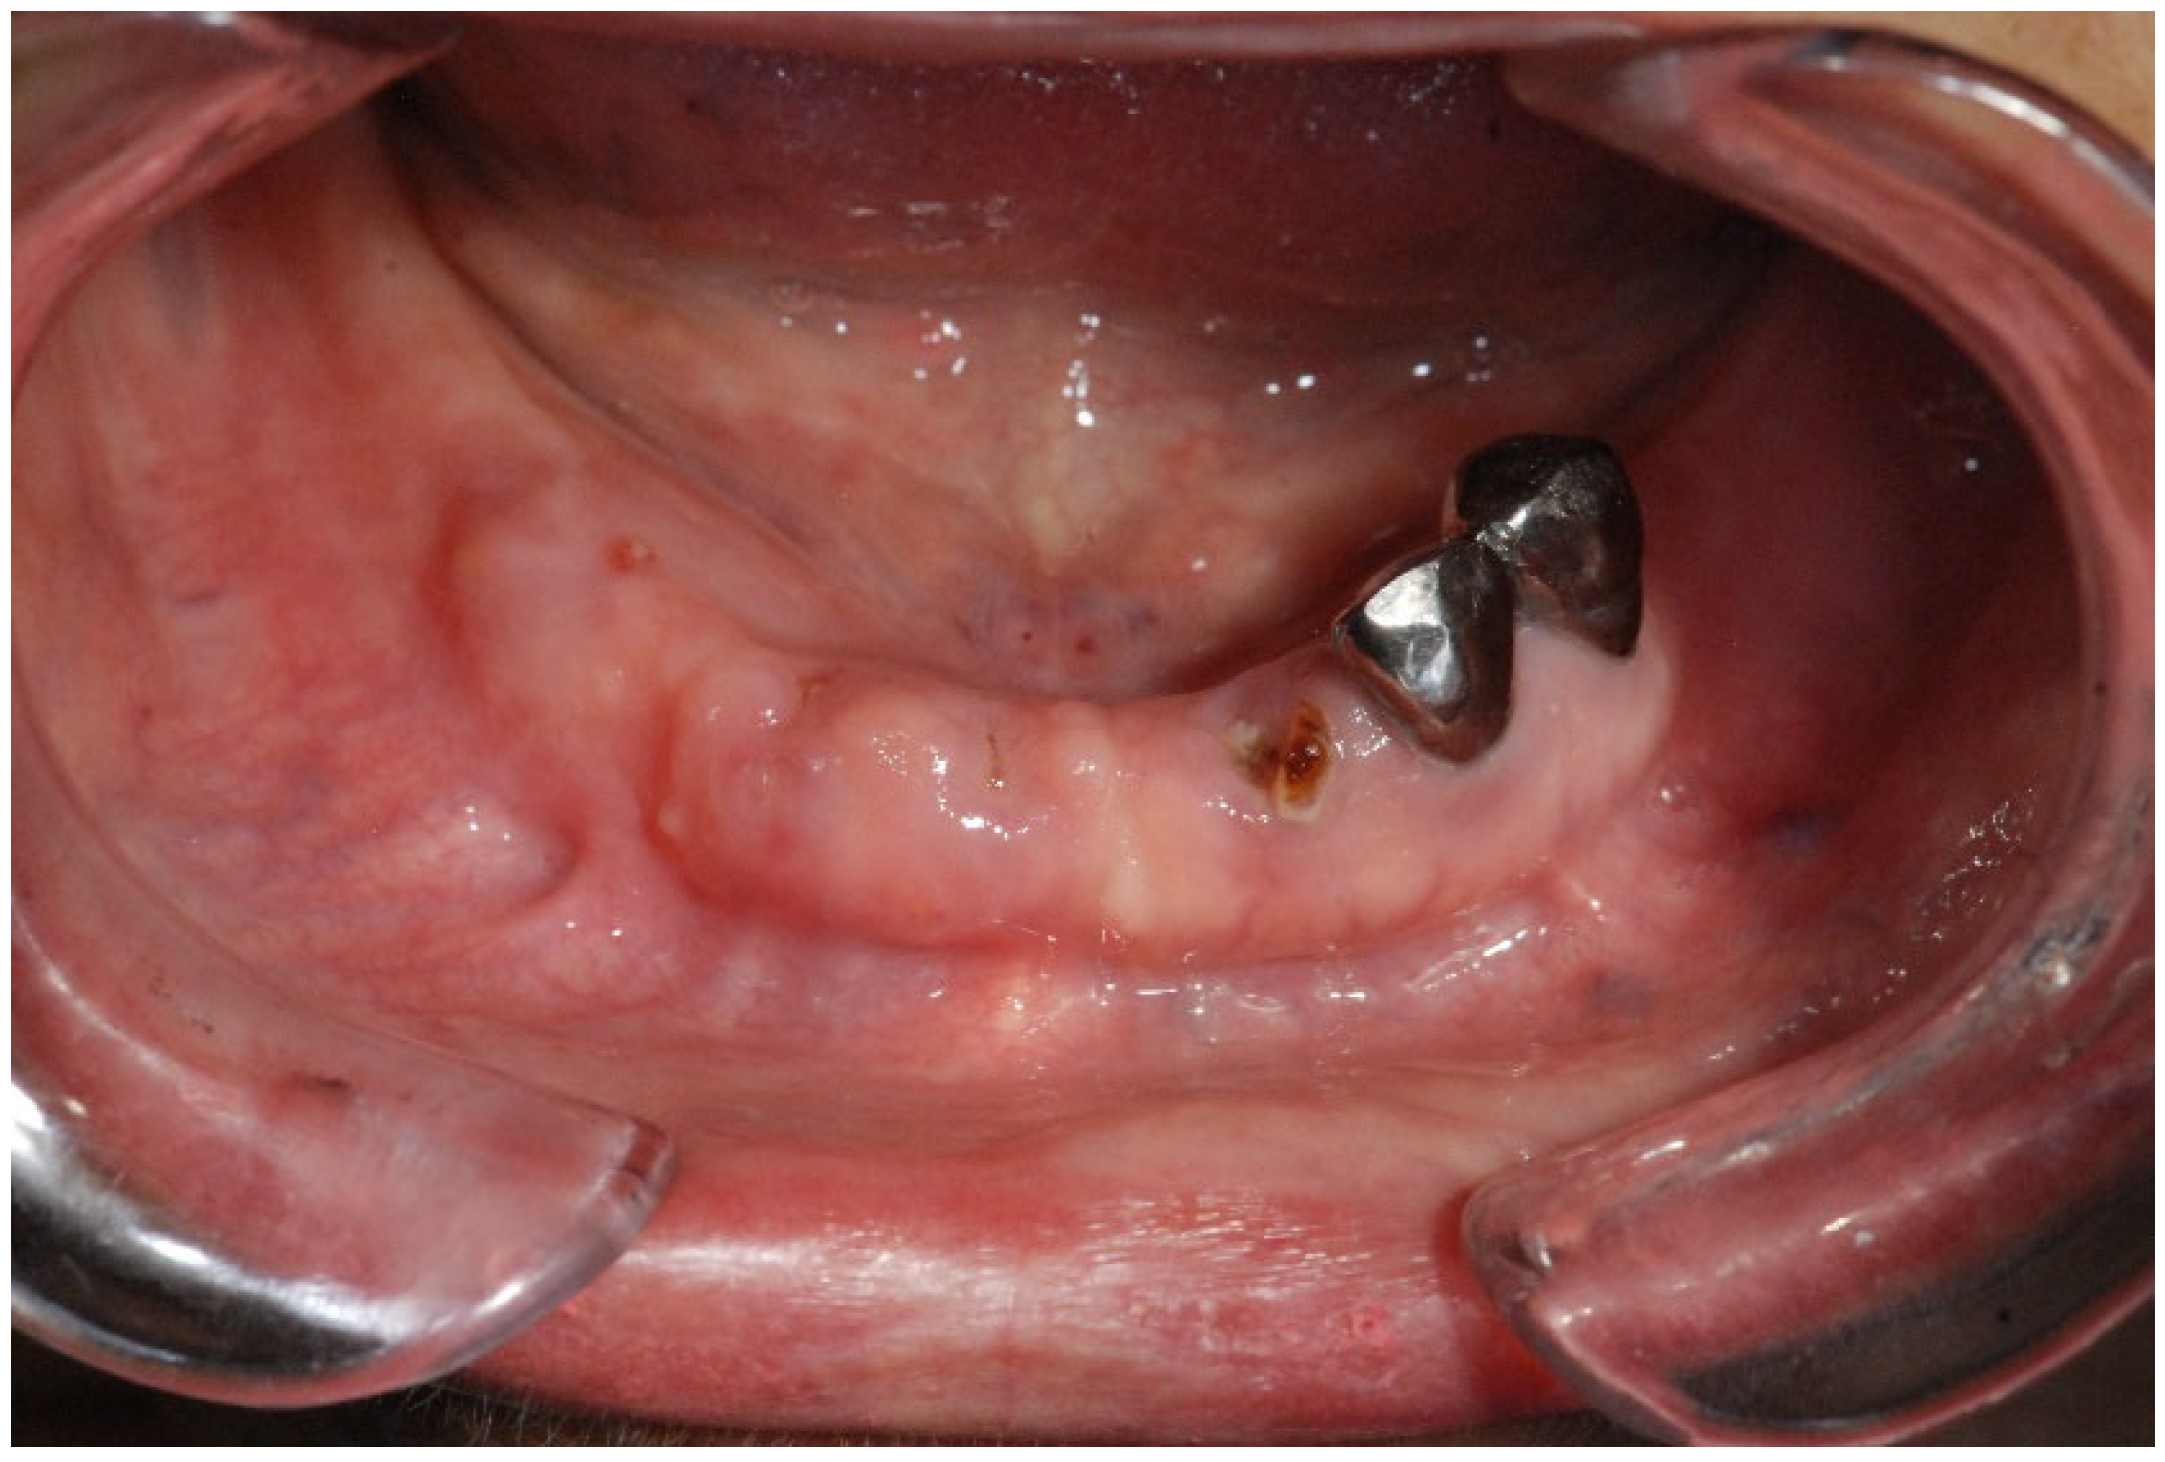

| Fistula (Intraoral/Extraoral) | An abnormal tract that connects the oral cavity (or skin) to necrotic bone, allowing probing of the underlying bone tissue (Figure 4). | Stage 1+ |